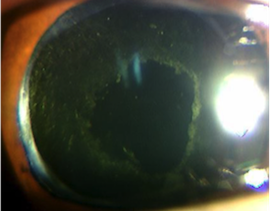

後発白内障の眼

後発白内障を治療した眼